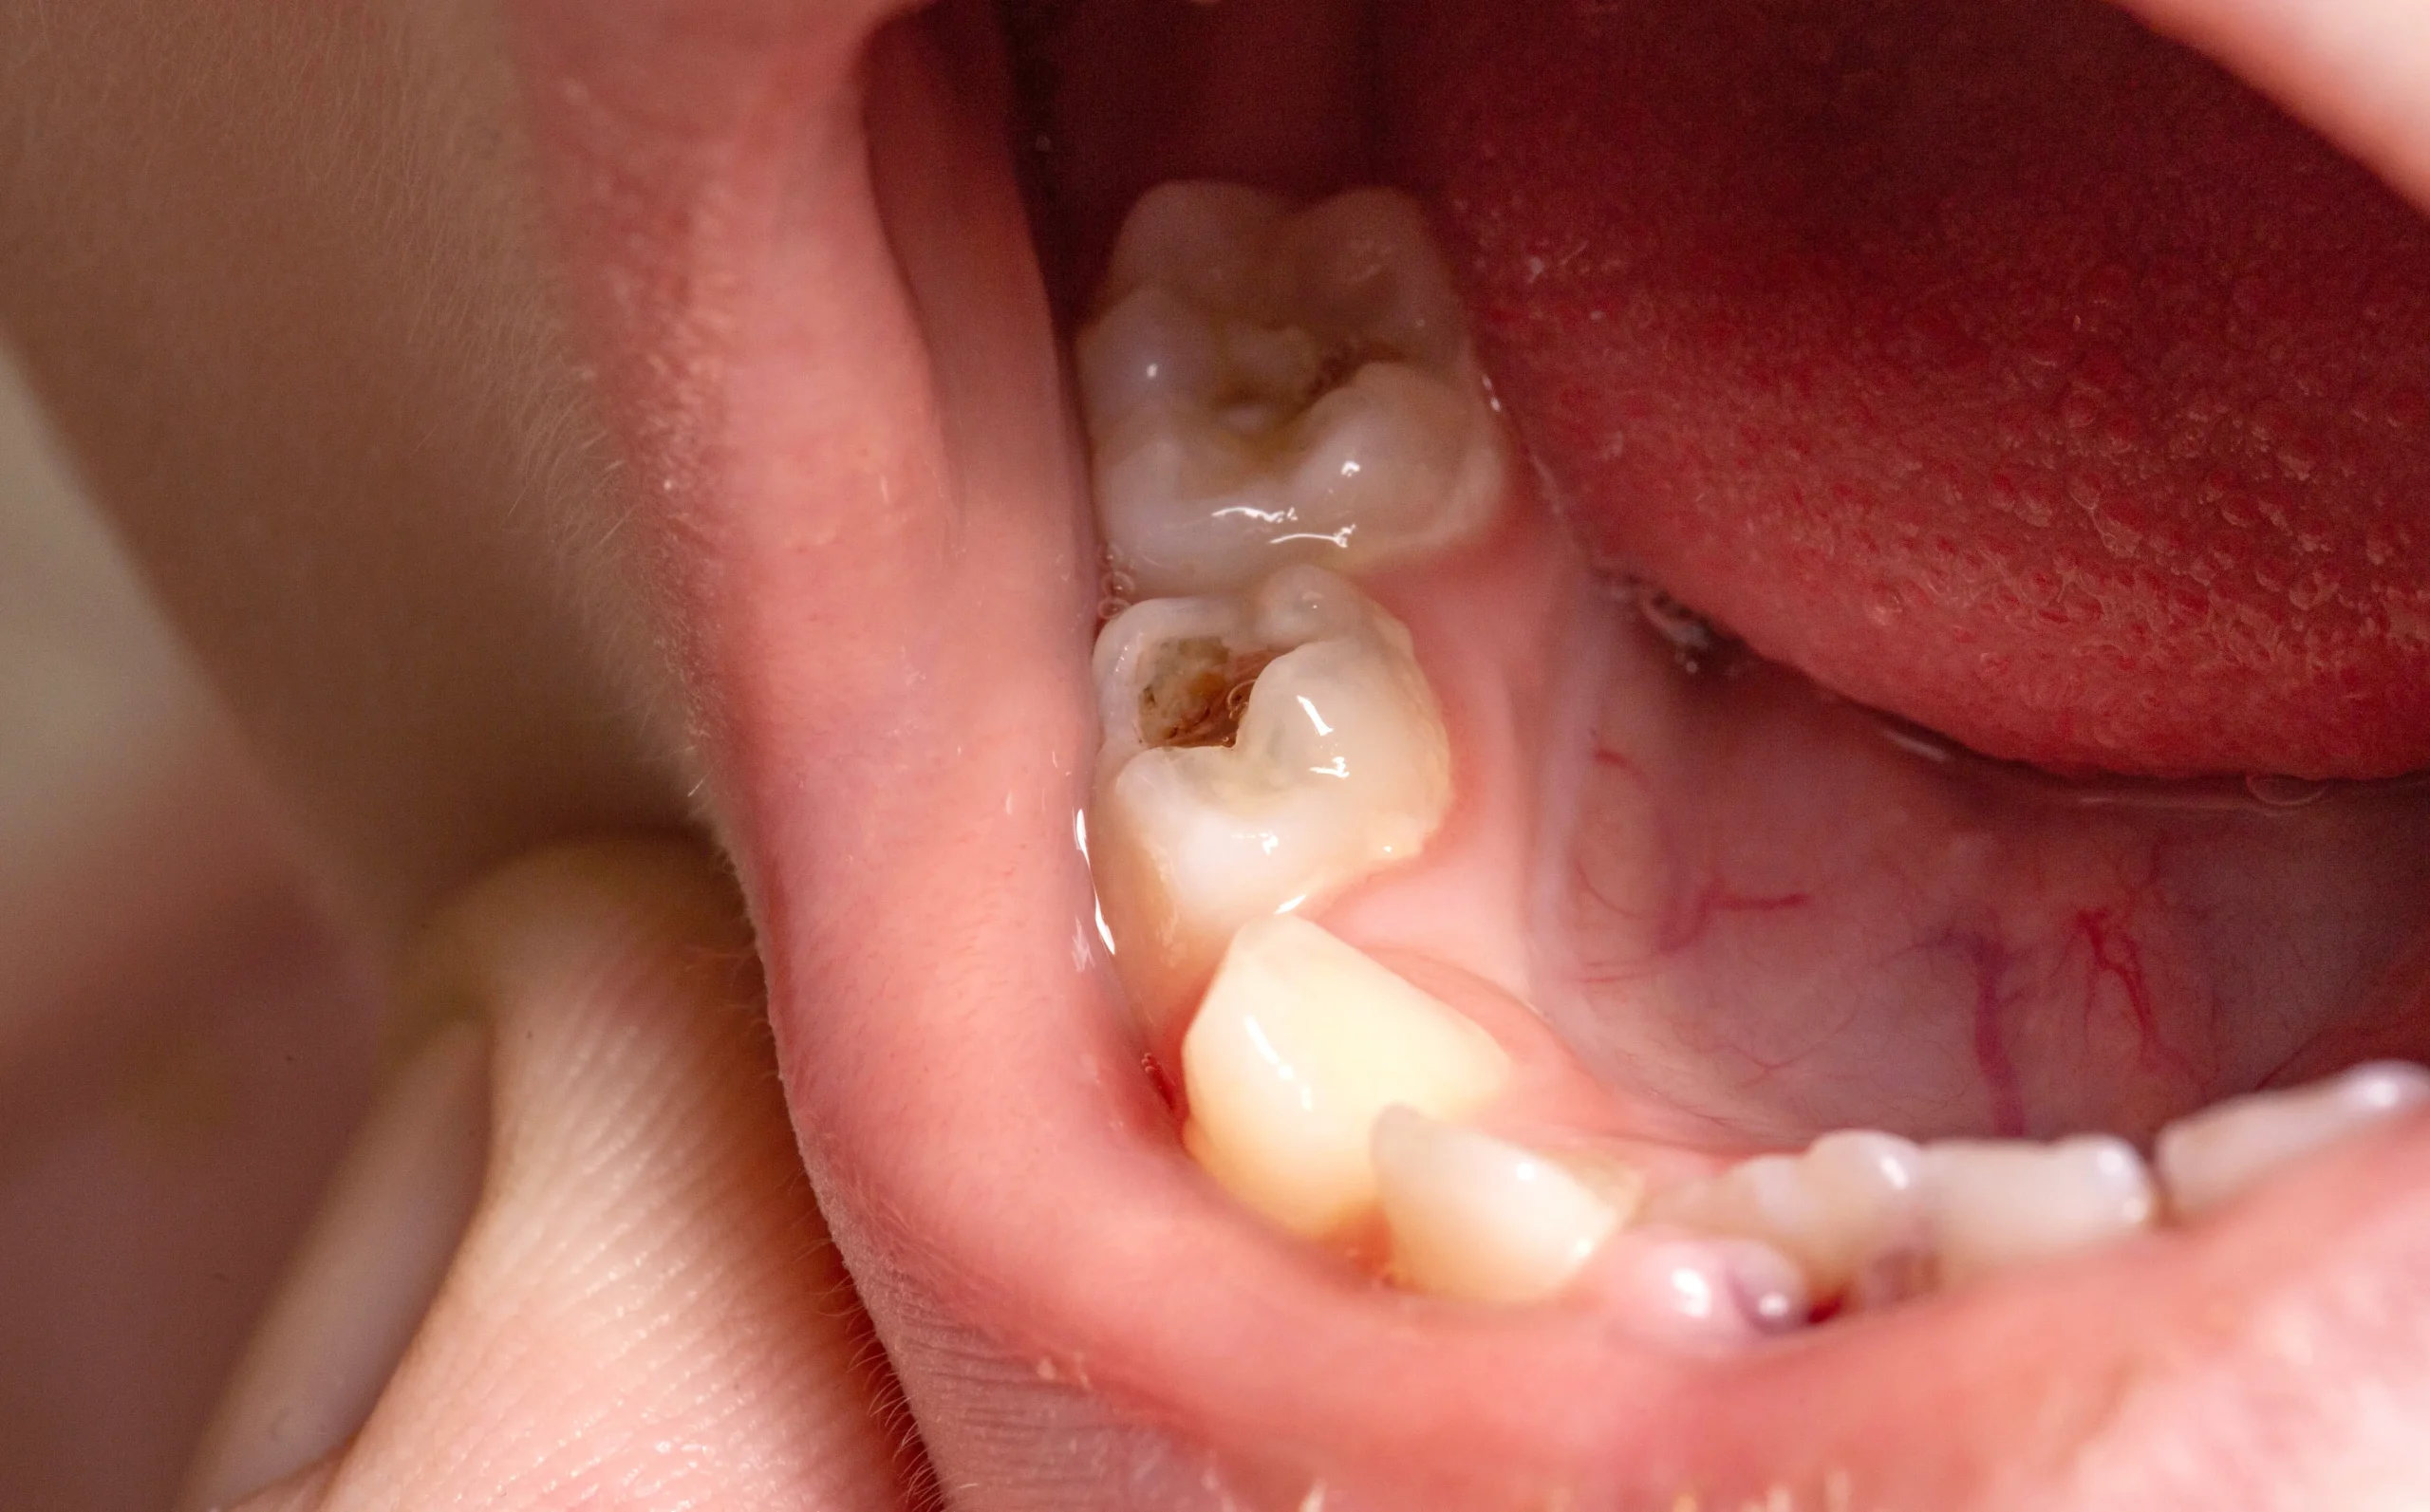

進行度合いは、C0(初期虫歯)、C1(エナメル質の虫歯)、C2(象牙質の虫歯)、C3(神経まで達した虫歯)、C4(歯根だけの状態)の5段階に分類されます。

C1:歯の表面(エナメル質)が侵食され、小さな穴があいた状態。痛みはないが、再石灰化では修復しきれないことが多く、削って詰める軽度な治療が必要な場合も。

C2:象牙質まで虫歯が進行。冷たいものがしみるなどの症状が出始めます。治療は詰め物やインレーを使います。

C3:虫歯が神経まで達した状態。ズキズキとした強い痛みがあり、根管治療(歯の神経を取る治療)が必要になります。

C4:歯の大部分が崩壊し、神経も死んでしまった末期状態。抜歯が必要なケースもあります。